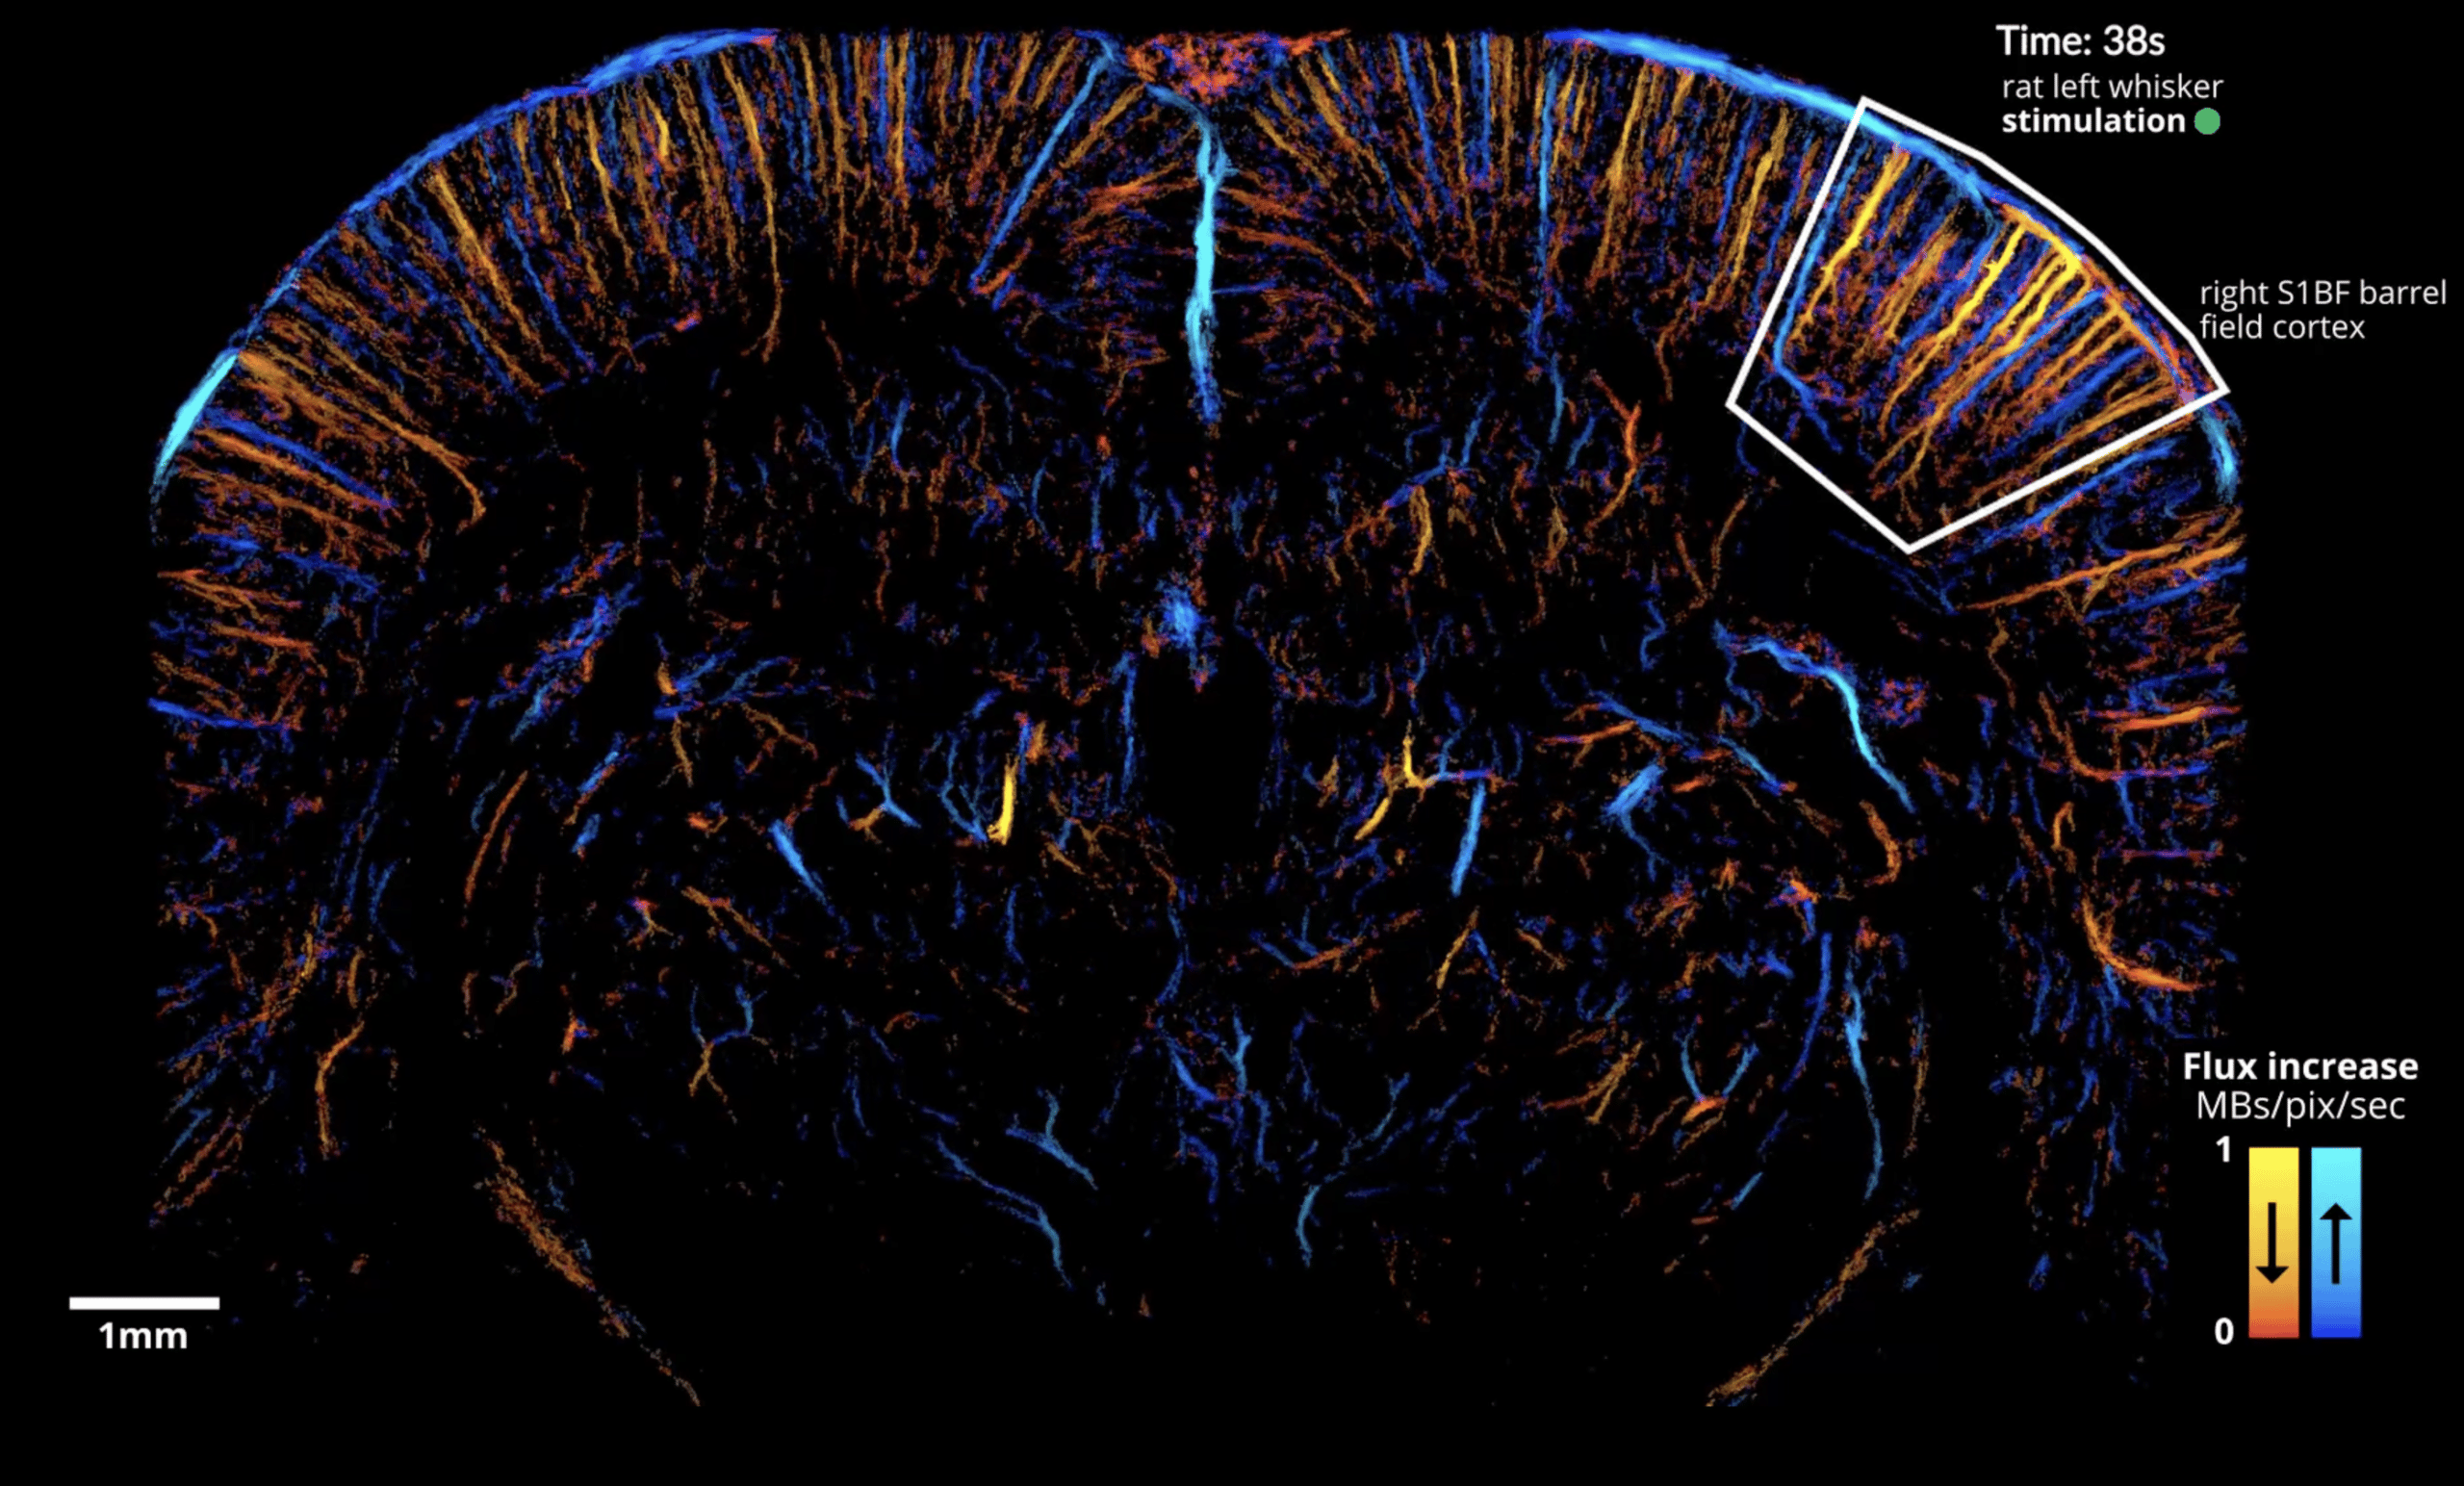

The paper, co-authored by members of the Iconeus team, provides an experimental protocol and data-processing pipeline for dynamic imaging of functional hyperemia (local increases in blood flow related to neuron activity) following whisker or visual stimulation in the rat. Instead of using the whole acquisition dataset to generate static ULM images, the paper reports how it’s possible to use a temporal ‘sliding window’ to construct dynamic maps instead, giving a temporal resolution of just 1 s.

The result is a map of functional hyperemia in both cortical and subcortical areas of the brain with a resolution of 6.5 µm – sufficient to discern the contributions from different vascular compartments across the brain at the same time. http://iconeus.com/wp-content/uploads/2022/08/fULM-nature.mp4Brain-wide microflow rendering of functional hyperemia in the rat brain detected by fULM during whisker stimulation. In common with other neuroimaging methods, we found that overlaying the data acquired from repeated stimuli helped to increase signal sensitivity and eliminate sparse signals for the smallest vessels. Reproduced from Renaudin et al., Nature Methods, 2022 (licensed under CC BY-4.0).

Importantly, the method is able to image the precapillary arterioles, which feature smooth muscle cells that have been shown to be the main controllers of cerebral blood flow. The results obtained also complement these earlier findings by showing that the relative increase in microbubble flow is actually greater in first-order capillaries and below. It also enables depth-dependent variation in blood speed to be understood, and quantifies the large increases of microbubble flux, blood speed and vessel diameter in venules during activation.